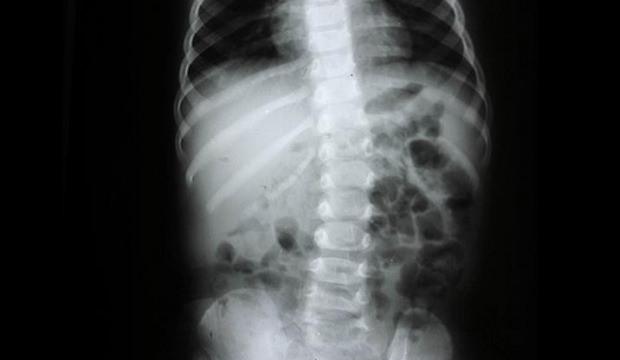

Kas ve iskelet sistemi sağlığında uyku pozisyonunun büyük önem taşıdığını belirten Doç. Dr. Hamza Sucuoğlu, “Günün yaklaşık 8 saati yatakta geçiyor. Bu süreç vücut için kritik bir önem sarf ediyor. Omurganın doğal eğriliklerinin korunması gerekiyor. Bu yüzden yatak ve yastık, vücudun anatomik yapısına uygun olmalı. Omurganın fizyolojik eğrileri korunmazsa kas spazmları, eklem problemleri ve kronik ağrılar ortaya çıkabilir. Özellikle yan yatış daha sağlıklı bir seçenek. Sırtüstü yatışta da omurgayı destekleyen ürünlerin tercih edilmesi gerekir.” dedi.

Yatak seçiminde en sık yapılan hatanın çok sert ya da çok yumuşak ürünleri tercih etmek olduğunu ifade eden Doç. Dr. Sucuoğlu, “Orta sertlikte ve vücut formunu destekleyen yataklar en ideali. Özellikle viskoelastik ve lateks yataklar hem anatomik uyum hem de hava geçirgenliği açısından avantaj sağlıyor. Çökmüş, deforme olmuş yataklar omurganın doğal yapısını bozar. Bu da uzun vadede bel ve boyun fıtıklarına zemin hazırlar.” diye konuştu.

Yastık seçiminin en az yatak kadar önemli olduğunu vurgulayan Doç. Dr. Sucuoğlu, “Boyun boşluğunu desteklemeyen yastıklar ciddi sorunlara yol açabiliyor. Çok yüksek ya da çok alçak yastık kullanımı boyun kaslarında kasılmalara neden olur. Bu durum zamanla boyun düzleşmesi ve fıtık gelişimine zemin hazırlar. Omuz yüksekliğine uygun, orta sertlikte ve boyun boşluğunu dolduran ortopedik yastıkların tercih edilmesi gerekir. Özellikle boyun fıtığı olan hastalarda doğru yastık kullanımı tedavinin önemli bir parçasıdır.” şeklinde konuştu.